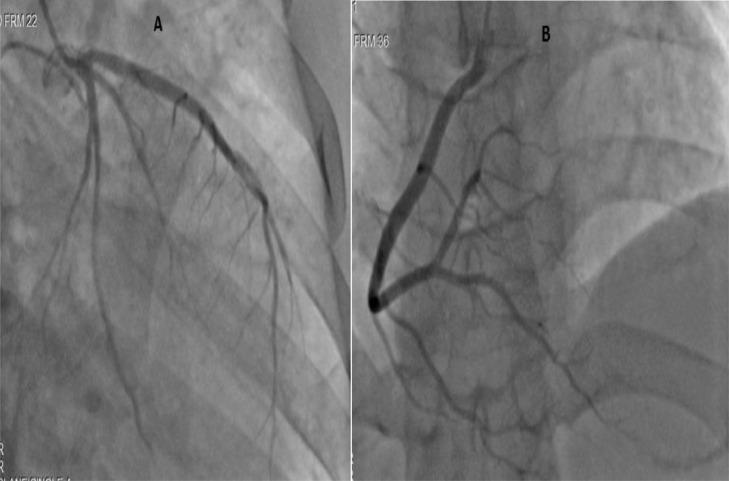

We report the case of a 23 years old patient who developed an acute myocardial infarction one day after his second dose of COVID-19 BIBP vaccination, complicated by severe left ventricle systolic dysfunction with an ejection fraction measured at 32%, associated with left ventricular wall motion abnormalities well evolved under treatment of heart failure with reduced EF combining :angiotensin-converting enzyme inhibitor, beta blocker, mineralocorticoid receptor antagonists and sodium-glucose cotransporter 2 inhibitors. Coronary arteries were normal at angiography suggesting initially the diagnostic of myocarditis. Therefore, a cardiac magnetic resonance imaging was performed to confirm the latter, which showed an image consistent with a recent left ventricular subendocardial infarction, remarkably prominent in the left anterior descending artery territory and the absence of signs of myocarditis. The patient had no previous past medical history or other clinical features explaining this coronary event onset. Thus, the vaccine was potentially to be implicated in the pathophysiology of the event. Overall, complications associated with COVID-19 vaccines are extremely rare, and their benefit is well established. That's why they continue to be recommended by public health experts despite of their rare side effects.

我们报告了一例23岁患者的病例,该患者在第二次接种新冠病毒灭活疫苗一天后发生急性心肌梗死,并发严重左心室收缩功能障碍,射血分数为32%,伴有左心室壁运动异常,在射血分数降低的心力衰竭治疗中病情好转,治疗方案包括联合使用血管紧张素转换酶抑制剂、β受体阻滞剂、盐皮质激素受体拮抗剂和钠-葡萄糖协同转运蛋白2抑制剂。血管造影显示冠状动脉正常,最初提示诊断为心肌炎。因此,进行了心脏磁共振成像以确诊,结果显示图像与近期左心室心内膜下梗死相符,在左前降支动脉区域尤为明显,且无心肌炎迹象。该患者既往无病史或其他临床特征可解释此次冠状动脉事件的发生。因此,疫苗可能与该事件的病理生理机制有关。总体而言,与新冠病毒疫苗相关的并发症极为罕见,其益处已得到充分证实。这就是尽管存在罕见的副作用,公共卫生专家仍继续推荐接种疫苗的原因。